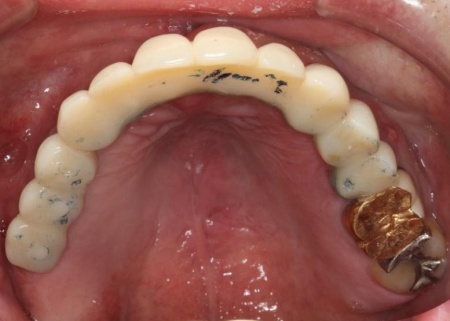

拝見したところ、右上奥歯4本が欠損しており、その影響で全体の噛み合わせのバランスが崩れていました。

加えて、噛んだときに上下の歯の中心がずれており、顔貌のゆがみにもつながっています。

欠損部が多い状態が長期間続いたことで噛み合わせが低く、新しい歯を入れるための高さも不足していました。

また、右上前歯も1本欠損しており、両隣の歯を土台として橋を渡すように連結した被せ物「ブリッジ」が装着されていましたが、土台となっている右上前歯2本(中切歯、犬歯)が割れており、温存が難しい状態です。

さらに、劣化してうまく適合していない被せ物、詰め物、既存のインプラントが複数見られ、これらも噛み合わせを乱す原因となっていました。

インプラントが骨にしっかりとなじんだことを確認したら、白くて強度の高い人工歯「ジルコニアクラウン」を装着しました。

また、インプラント治療と並行して、合わなくなっていた被せ物・詰め物・既存のインプラントを作り替えます。

左上奥歯は、装着されていた金属の古い詰め物を外し、白い樹脂を直接詰める「ダイレクトボンディング」で修復しました。

他院で治療を行った左下奥歯3本のインプラントは、土台をそのまま活かして人工歯だけ作り直し、噛み合わせを調整します。

左下奥歯1本、右下奥歯2本に装着されていた古い被せ物はすべて外し、ジルコニアクラウンと交換しました。

最後に、見た目や噛み合わせに問題がないかを確認し、治療を終了しています。